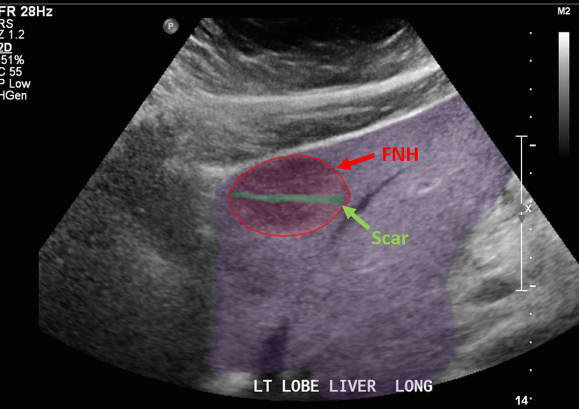

FNH (Focal Nodular hyperplasia) US finding

- spokewheel vascularity

- iso-hyperechoic mass

- hypoechoic lesion with central scar

- fatty liver

위에서 보인 초음파소견처럼 FNH는 경계가 명확한 균일한 종괴이며 내부에 섬유성 반흔이 있다. 에코는 저에코를 갖지만 간혹 고에코나 등에코등 다양하게 나타날 수 있으며 피막이 없다. 도플러상 과혈관성을 보이며 정상 간세포조직을 갖는다. 초음파 만으로 간암과 구별할 수 없으므로 혈액검사, CT 와같이 다양한 검사를 통한 진단이 필요하다.